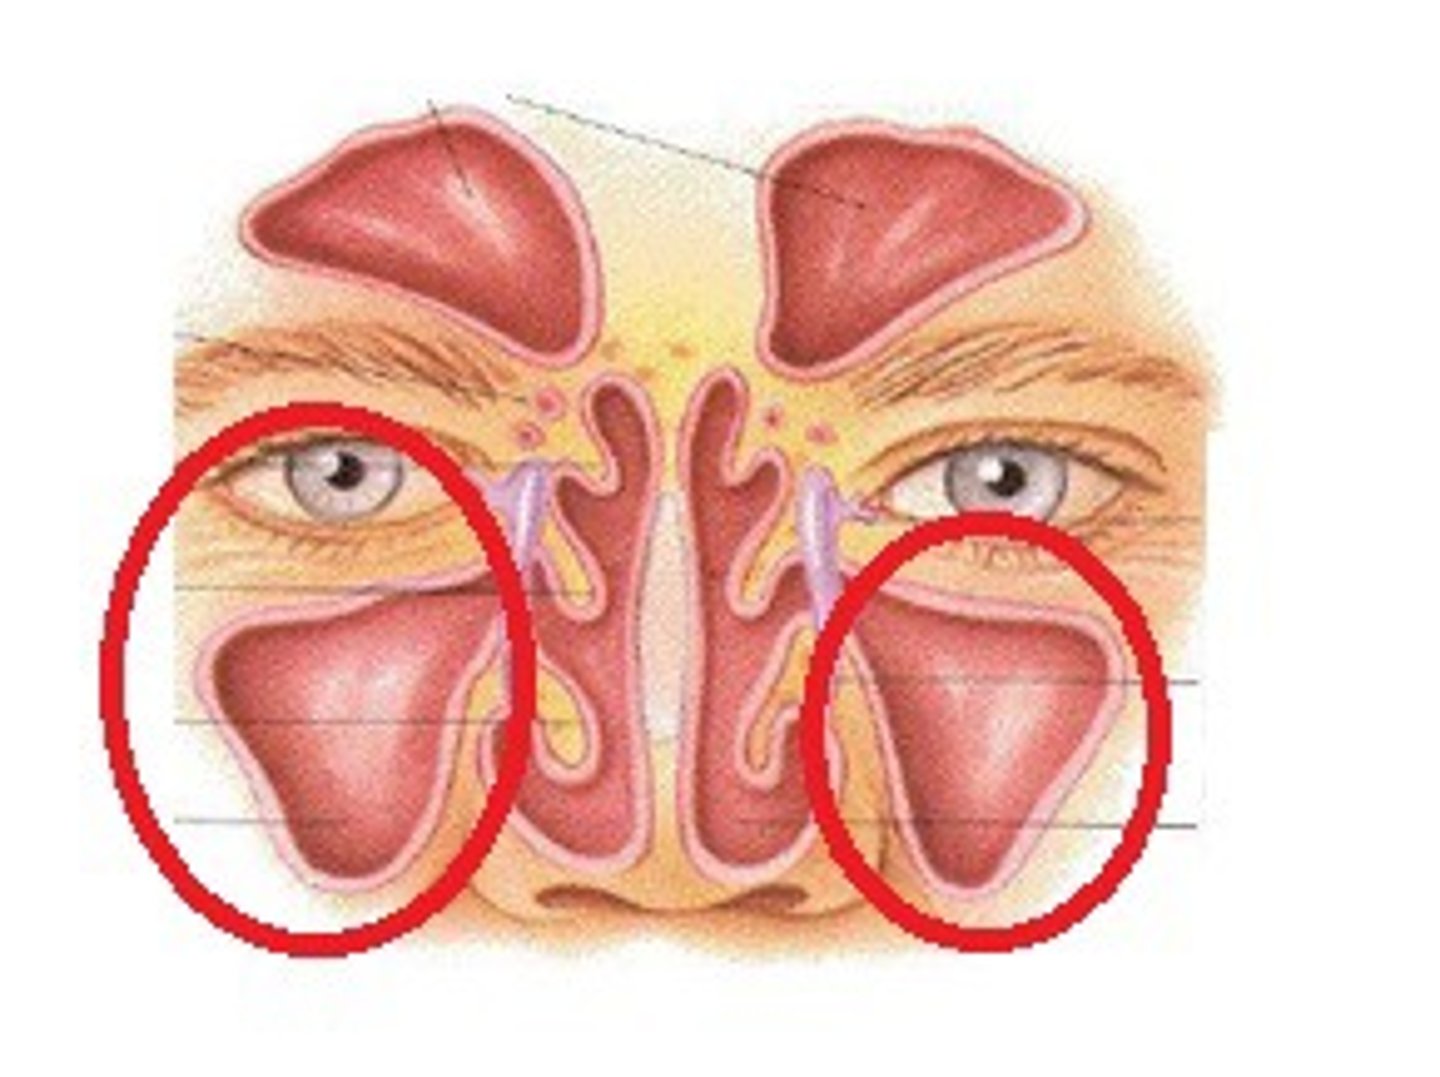

Concha nasalis

Nosies kriauklės

sinus maxillaris

Viršutinio žandikaulio antis

Cavitas nasi

nosies ertmė